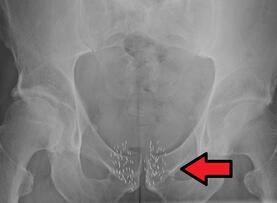

如果生物标志物的确可以控制前列腺癌细胞的生长,那么其或许是之前研究者并未见过的一种新的信号,而且其可以为开发治疗前列腺癌的新型药物提供思路;而这种新型的生物标志物也可以帮助区分快速发展和缓慢发展中的肿瘤组织。文章中研究者在骨质细胞中发现了这种调剂性的机制,随后他们还发现这种机制在前列腺癌细胞中或许是可以进行操作的。